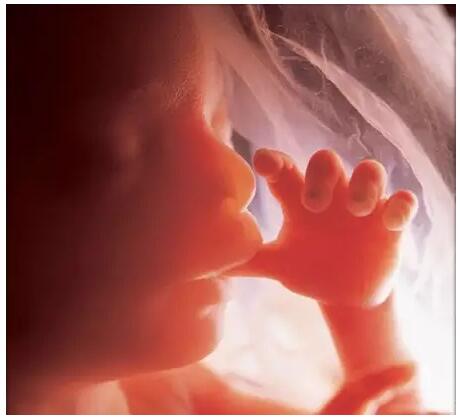

女人一旦怀孕了,那就意味着自己在不久的将来就要做妈妈了,在怀孕期间,宝宝在妈妈们的肚子里面就已经开始正常的生活,不仅仅会笑还会哭呢?那您知道胎儿在子宫内哭泣为啥吗?您知道胎儿在子宫里干什么了吗?今天小编就为您介绍一下。

只要不睡觉的话,他就是一个精力充沛、调皮好动的小家伙,到处游走、活动筋骨、吸手指、甚至是啃自己的小脚丫。

其实,在还不能称为“胎儿”时,他就开始在妈妈的子宫内四处游动了,这种漫无目的的游动没有什么姿势可言,像只悠闲的小海马。这一活动从胎宝宝6周大一直持续到怀孕后期,直到他的个头大得不能漂浮在羊水中才算结束。

他能自由地移动胳膊,弯曲手指和脚趾,还能弯曲、伸展并转动手掌、手腕、双腿和脚趾。

到了怀孕后期他的骨头变得越来越硬后,他会常常翻身,乱踢一通,还能握手、张开手,孕妈妈会感到胎儿在腰的两边滑动。这都是胎儿在活动筋骨、做运动。